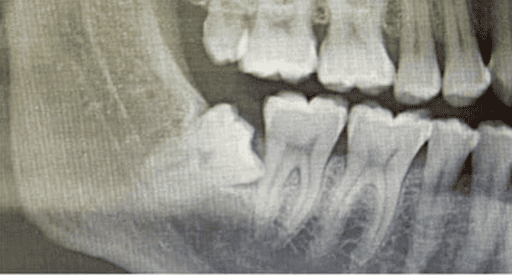

While comprehensive benchmarks exist for evaluating editing models on natural images Lin et al. (2015); Huang et al. (2023); Xia et al. (2021), their adaptation to medical images remains challenging. Here, even minor alterations can carry significant clinical meaning, demanding high editing precision, semantic fidelity, and anatomical correctness. Text-guided medical image editing holds substantial clinical potential, as it could highlight lesions in CT scans Guo et al. (2023), simulate surgical outcomes Huang et al. (2025), or generate personalized teaching materials Lee et al. (2024). Such applications promise direct benefits to diagnosis, treatment optimization Ma (2025), and training Zhang et al. (2024a). Despite the versatility of current models, they often fail at clinically meaningful transformations that are intuitive to general physicians or even non-experts. For example, InstructPix2Pix Brooks et al. (2023a) can successfully handle prompts such as “Add a missing key on a piano keyboard” but fails on similar medical prompts such as “Add a missing tooth in this dental image” (see Fig. 1). Notably, this failure cannot be resolved by adjusting the text or image guidance scales Brooks et al. (2023b) (see Fig. 7), where the text guidance scale controls the classifier-free guidance weight for the text prompt, and the image guidance scale controls the conditioning strength on the input image during denoising. This underscores the difficulty of transferring such models to domains that require fine-grained anatomical understanding and specialized domain knowledge Kazerouni et al. (2022); Ayana et al. (2024).

Figure 7 illustrates the limitations of controlling text and image guidance scales in diffusion-based image editing. Specifically, for the task of “adding a missing tooth,” varying these scales fails to yield a satisfactory result when using the InstructPix2Pix model. While increasing the text guidance scale emphasizes the semantic prompt, and higher image guidance preserves visual fidelity to the original image, neither direction successfully produces the desired anatomical modification. This outcome suggests that simply tuning global guidance weights is insufficient for achieving fine-grained, localized edits in medical or detail-critical domains. As shown in Figure 7, the generated outputs either omit the new tooth entirely or introduce unnatural artifacts, underscoring the need for more controllable and spatially-aware editing approaches.

Edit Prompt: “Remove the wisdom teeth.”

Description of Expected Change: “Panoramic dental radiograph: Wisdom teeth in the upper and lower jaws were removed, resulting in a post-surgical appearance with space in the alveolar bone where the teeth previously resided.”